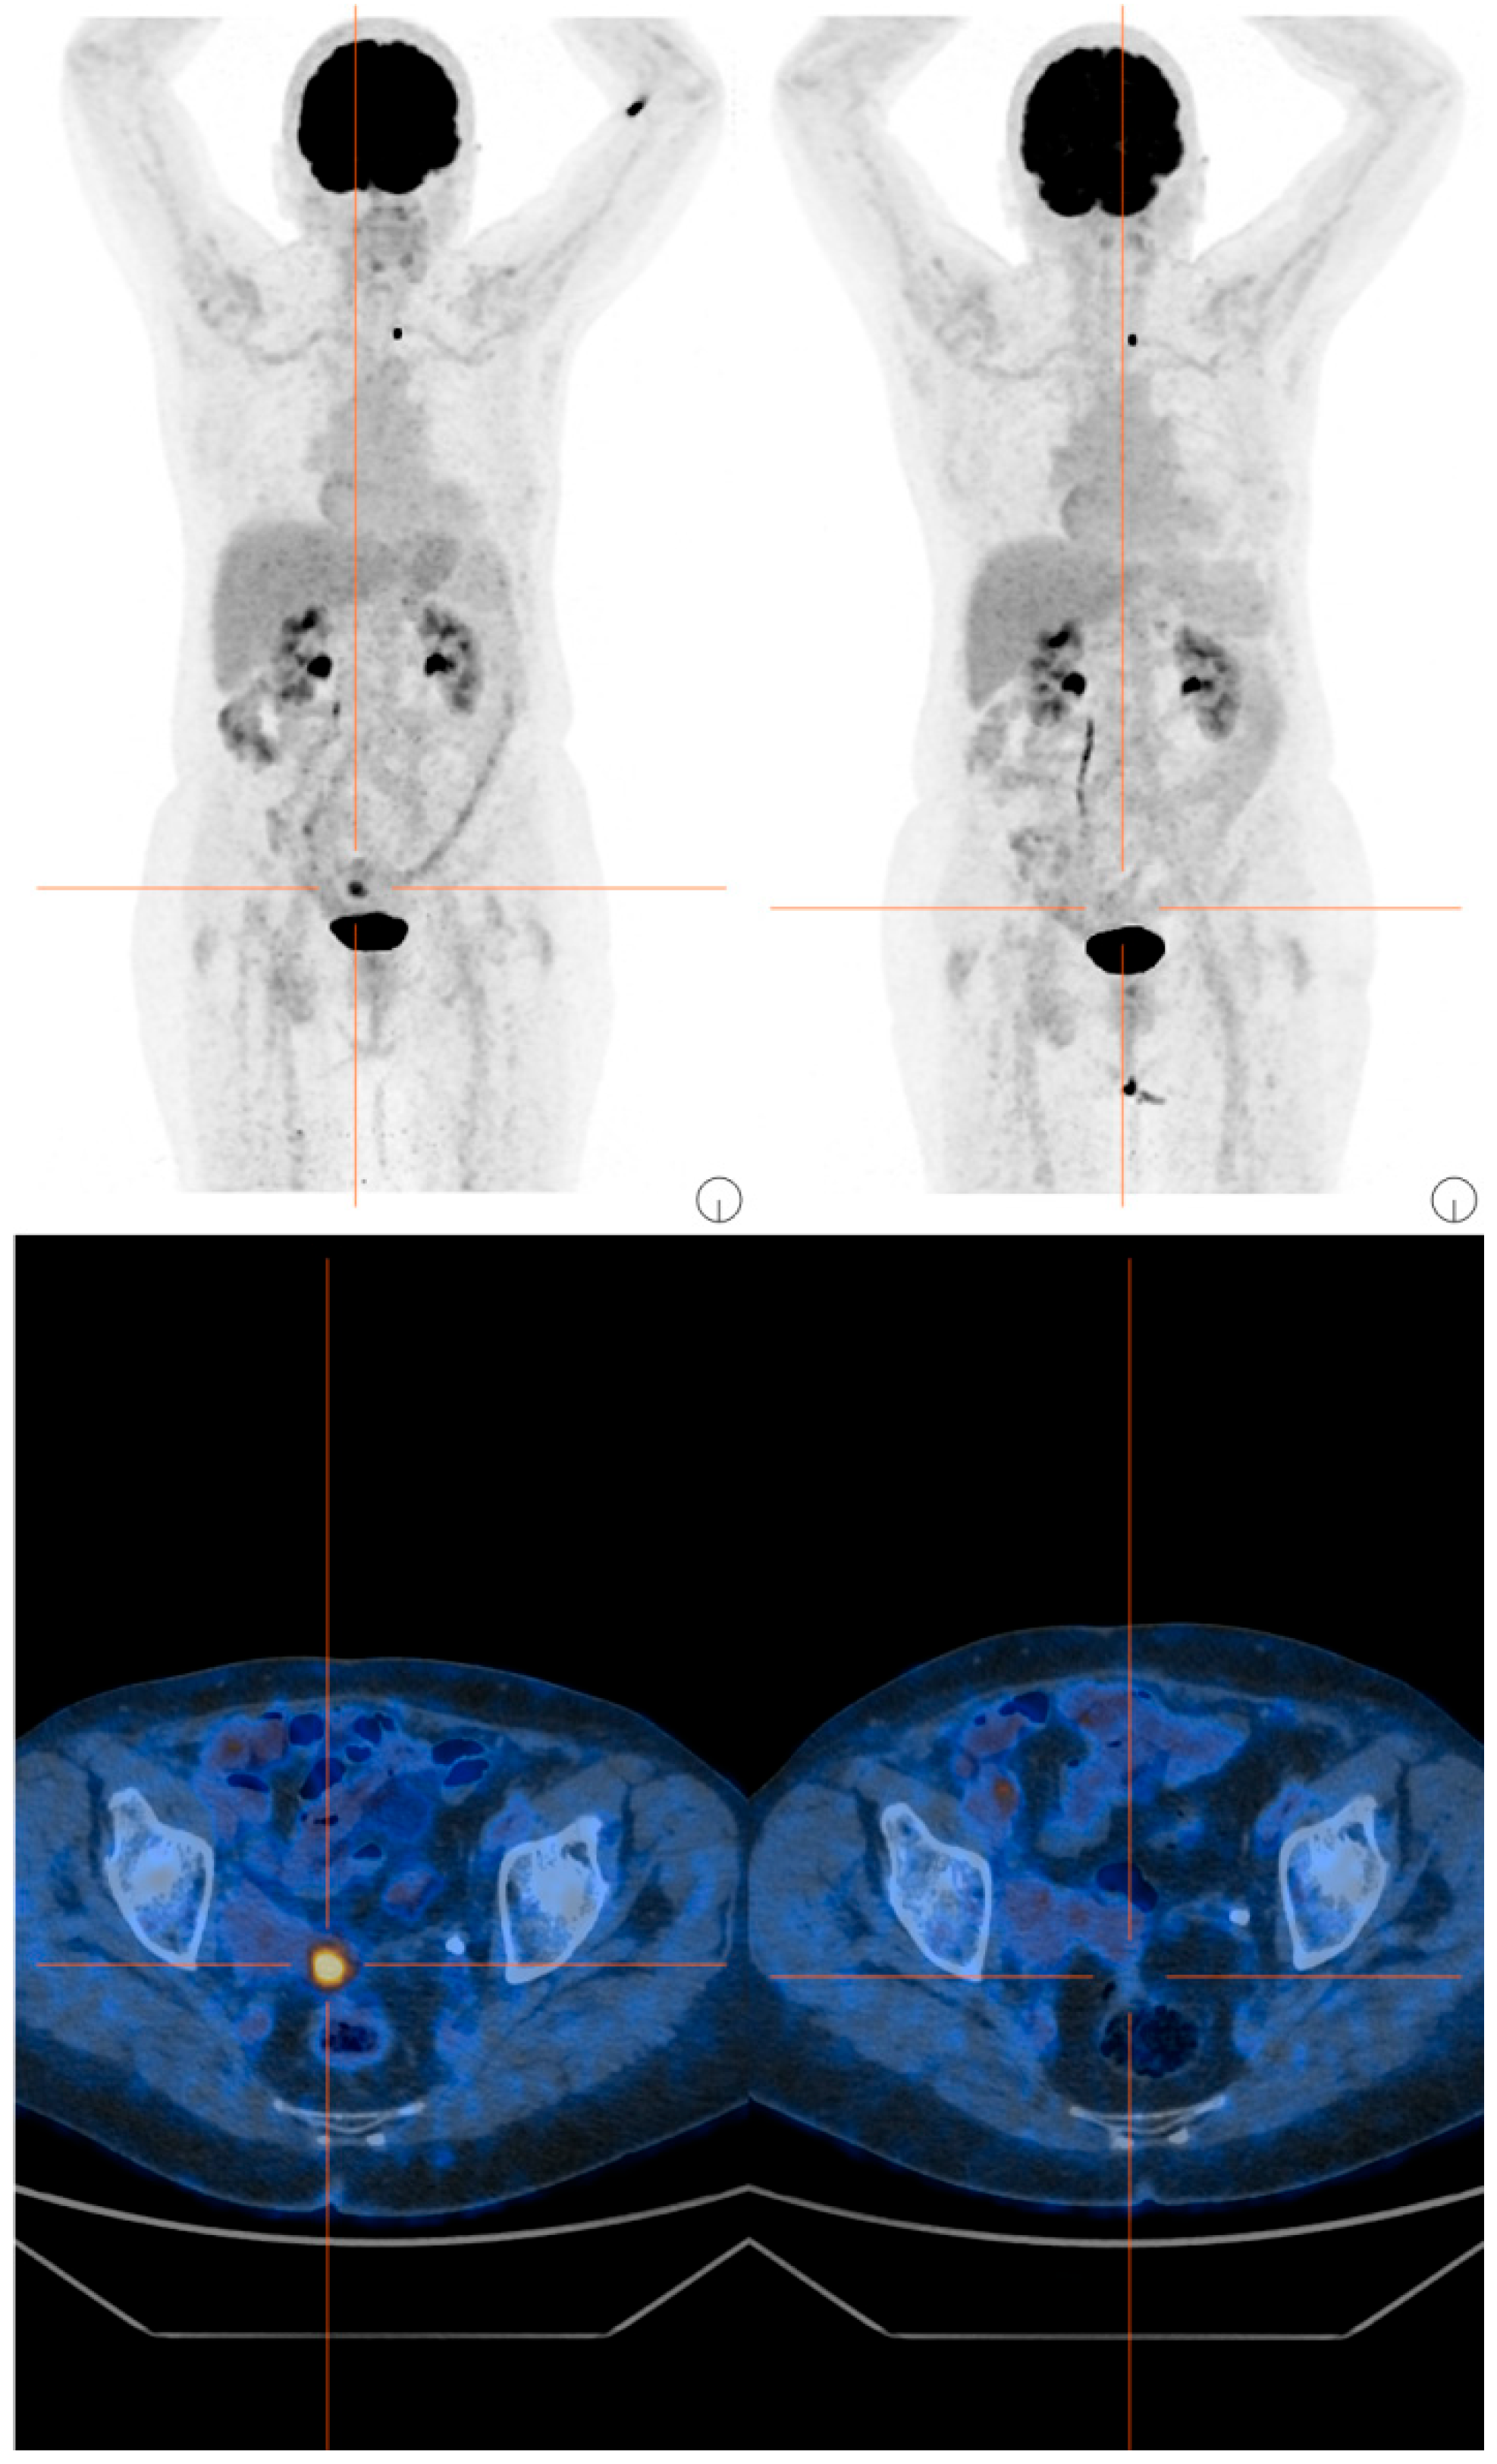

2. Case Presentation